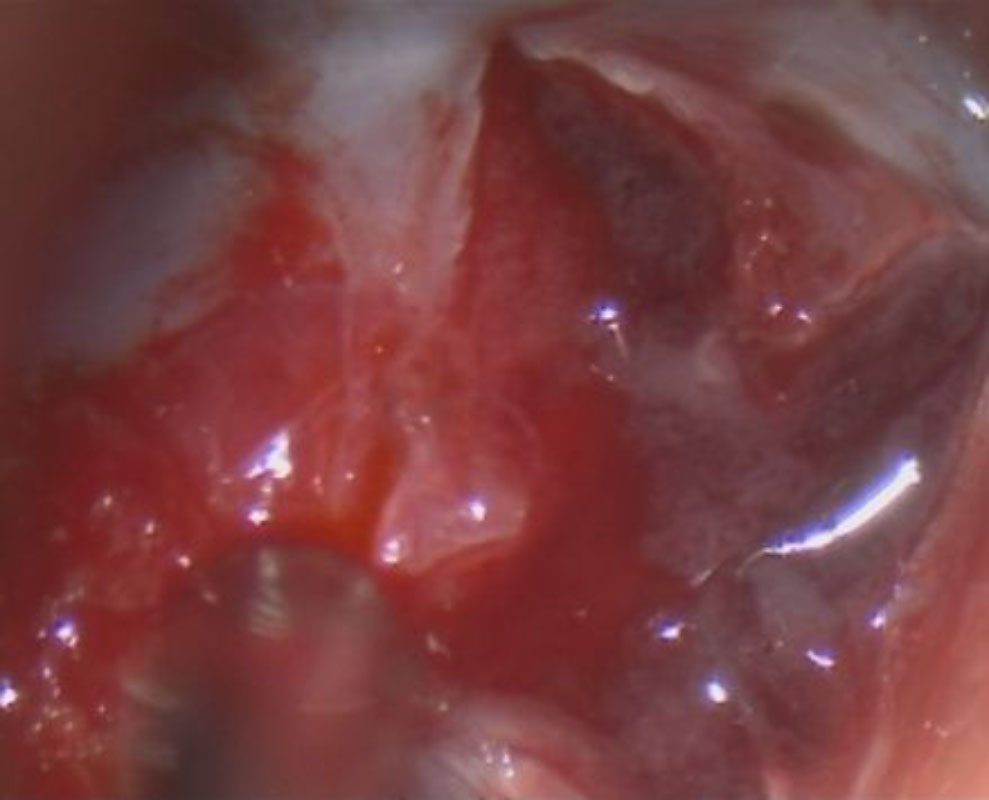

567

'24年9月

40代

小脳血管芽腫

頭蓋内腫瘍摘出術

No.’24_69 手術前1

No.’24_69 摘出 前

No.’24_69  摘出 中

No.’24_69 摘出 後